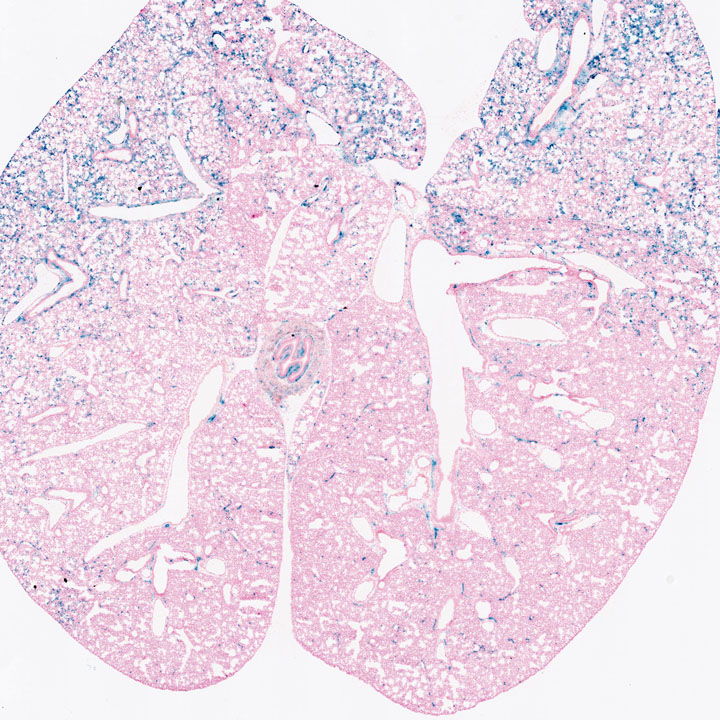

Respiratory System

Images

Drag images to compare to others or to data in the table below. Drag corners to resize images for more detail.

Recombinase Activity